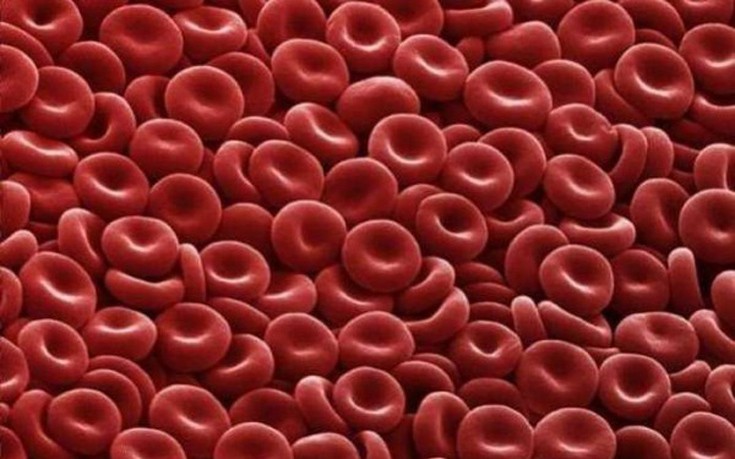

Αιμοπετάλια